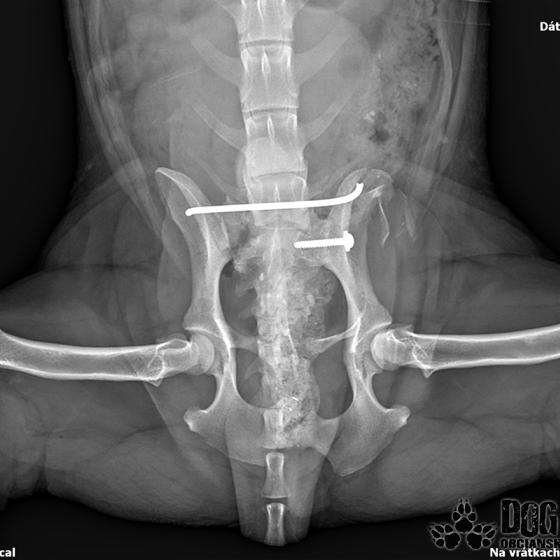

Karola nám doviezla pani, ktorá ho našla, asi jediná dobrá duša, ktorá pri ňom neprešla so zatvorenými očami. Ihneď sme s krpcom utekali na veterinu aby sa zistila závažnosť jeho zranení. Hneď pri prvých RTG snímkoch sa ukázala obojstranná fraktúra panvy, taktiež fraktúra krídla panvy a keby mu to chudákovi nestačilo, do tretice sa objavila zlomenina stavca. Karolko mal neznesiteľné bolesti, ale krásne prečkal vyšetrenie lebo vedel, že je v dobrých rukách a dostáva sa mu pomoci. Po nálezoch sme okamžite kontaktovali neurológiu a ortopédiu na veterinárnej klinike Sibra - centrum veterinárnej medicíny, kde sme dostali hneď termín na príjem.

Karol nemá žiadne neurologické deficity, po ortopedickej operácii bude vedieť behať a bez problémov bude vedieť samostatne cikať a kakať. Po tejto úžasnej správe sme samozrejme dali zelenú náročnej ortopedickej operácii pod vedením MVDr. Vatolíka. Operácia sa podarila na výbornú, Karči je "zoskrutkovaný" a vôbec nič mu nebráni v tom, aby opäť mohol behať a aktívne žiť. Momentálne sa zotavuje po operácii, musí mať prísny kľudový režim. Po vybratí stehov ho čaká hydro- a fyzioterapia, ktorá mu pomôže postaviť sa na nohy. Je to bojovník, veľmi sa chce uzdraviť a v jeho očkách je dokonale vidieť, že už kuje plány čo všetko zameškané bude musieť dobehnúť.